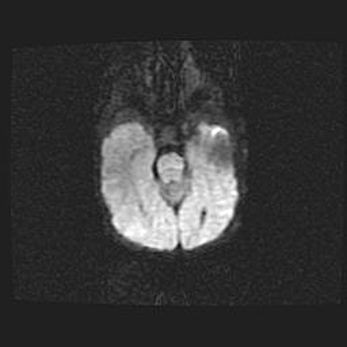

Церебральная ишемия II.

Возраст: 5 дней

Вес: 3400 г

Пол: женский

Окружность головы: 35 см

Срок гестации: 39 недель

Церебральная ишемия – это заболевание, характеризующееся недостаточностью (гипоксией) либо полным прекращением (аноксией) снабжения мозга кислородом по причине закупорки одного или нескольких сосудов. Это приводит к  что метаболическим расстройствам различной степени тяжести в тканях головного мозга, развитию коагуляционных некрозов и гибели нейронов.